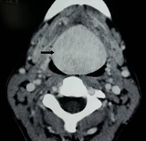

Renal clear cell carcinoma metastasis to submandibular gland: case report and review of the literature

F Higuera and others

Journal of Surgical Case Reports, Volume 2018, Issue 10, October 2018, rjy261, https://doi.org/10.1093/jscr/rjy261